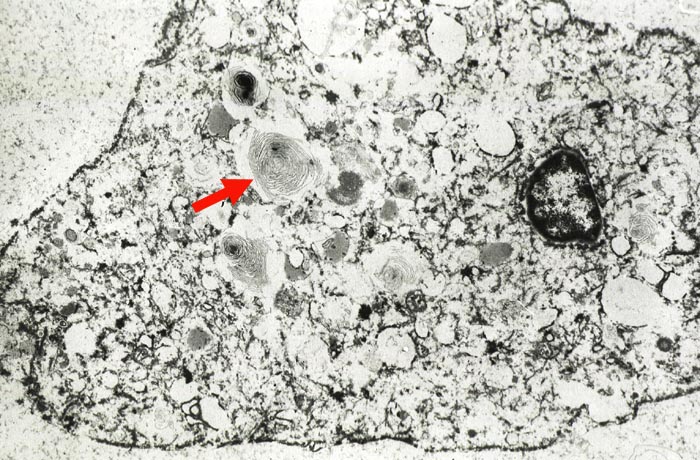

Das Antiarrhythmikum Amiodarone kann bei einem Teil der Patienten Lungeninfiltrate verursachen. Wichtigster Befund in der BAL ist eine Vermehrung der Makrophagen auf über 300x10^6/l. Viele Makrophagen sind zu Schaumzellen umgewandelt und am besten in der MGG Färbung an ihrem breiten fein vakuolären Zytoplasma erkennbar. Gleich aussehende Makrophagen werden auch im Pleuraerguss beobachtet. Daneben können Neutrophile, Eosinophile und Lymphozyten vermehrt sein. Die Makrophagen enthalten elektronenmikroskopisch darstellbare lamelläre Körperchen. Eine grosse Anzahl dieser Körperchen beweist einen Amiodaroneschaden.